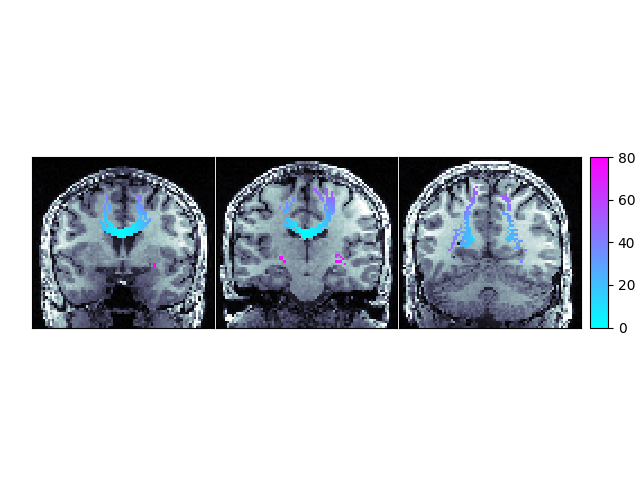

We will mask our WMPL to ignore values less than zero because negative numbers indicate no path back to the ROI was found in the provided streamlines

wmpl_show = np.ma.masked_where(wmpl < 0, wmpl)

slx, sly, slz = [60, 50, 35]

ax[0].matshow(np.rot90(t1_data[:, slx, :]), cmap=mpl.cm.bone)

im = ax[0].matshow(np.rot90(wmpl_show[:, slx, :]), cmap=mpl.cm.cool, vmin=0, vmax=80)

ax[1].matshow(np.rot90(t1_data[:, sly, :]), cmap=mpl.cm.bone)

im = ax[1].matshow(np.rot90(wmpl_show[:, sly, :]), cmap=mpl.cm.cool, vmin=0, vmax=80)

ax[2].matshow(np.rot90(t1_data[:, slz, :]), cmap=mpl.cm.bone)

im = ax[2].matshow(np.rot90(wmpl_show[:, slz, :]), cmap=mpl.cm.cool, vmin=0, vmax=80)

ax.cbar_axes[0].colorbar(im)

Path Length Map showing the shortest distance, along a streamline, from the corpus callosum ROI with the background set to -1.